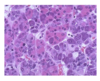

what types of cells are shown here?

Cells of the Anterior pituitary

- Pink ACIDOPHILS: secrete GH and PRL

- Dark purple BASOPHILS: secrete ACTH, TSH , FSH, LH

- Pale Chromophobs